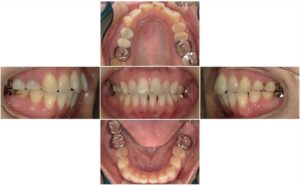

② 装置(ブラケット・バンド)を装着

その後、バンドとブラケットを歯につけ、ワイヤーを通して歯を動かし始めます。

⑤ 矯正の経過写真

矯正開始前と最新のお写真を掲載しています。

実際の変化が伝わりやすいので、ぜひご覧ください。

治療途中(現在)